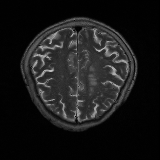

We obtain a subject-wise mean Dice score of 32.94% without any post-processing. By using a simple post-processing with erosion and dilation with filters, this number improves to 48.20% mean Dice score. In comparison, a similar study conducted by [3] consisting of a multitude of algorithms including AnoVAEGAN [4] and f-AnoGANS, obtained a best mean score of 27.8% Dice after post-processing by f-AnoGANS. Before post-processing the best method was Constrained AutoEncoder [8] with a score of 9.7% Dice. An exhaustive list is presented in Table 1. Figure 4 shows sample images of our results.

We obtain a subject-wise mean Dice score of 63.67% for the brain tumor segmentation. Utilizing a simple post-processing scheme of erosion and dilation with filter, we improve our mean Dice score to 68.01%. Figure 4 shows samples generated by our ASC-Net and Table 2 shows our before and after post-processing results. We attempted to apply f-AnoGANs [34] by following their online instructions and failed to generate good reconstructions as shown in Figure 5. The failure of AnoGANs in the reconstruction brings to light the issue with the regeneration based methods and the complexity and stability of GAN-based image reconstruction.

We obtain a slice-wise mean Dice score of 32.24% for this liver lesion segmentation, which improves to 50.23% by using a simple post processing scheme of erosion and dilation with filter. Sampled results are shown in Fig. 4. Compared with [42], which obtains a mean Dice score of 40.78% and a standard deviation of 0.43%, we improve the mean Dice score by almost 10%, but has a much larger standard deviation. Unlike [42], where the network is pre-trained on a artificial tumor dataset, and hence the pipeline customized for tumor segmentation, our method do not need such information beforehand. We notice that our standard deviation for BraTS dataset is similar to [27]. This is because novelty/anomaly detection algorithms without a pre-defined task would suffer from the co-morbidities issues discussed in Section 5.